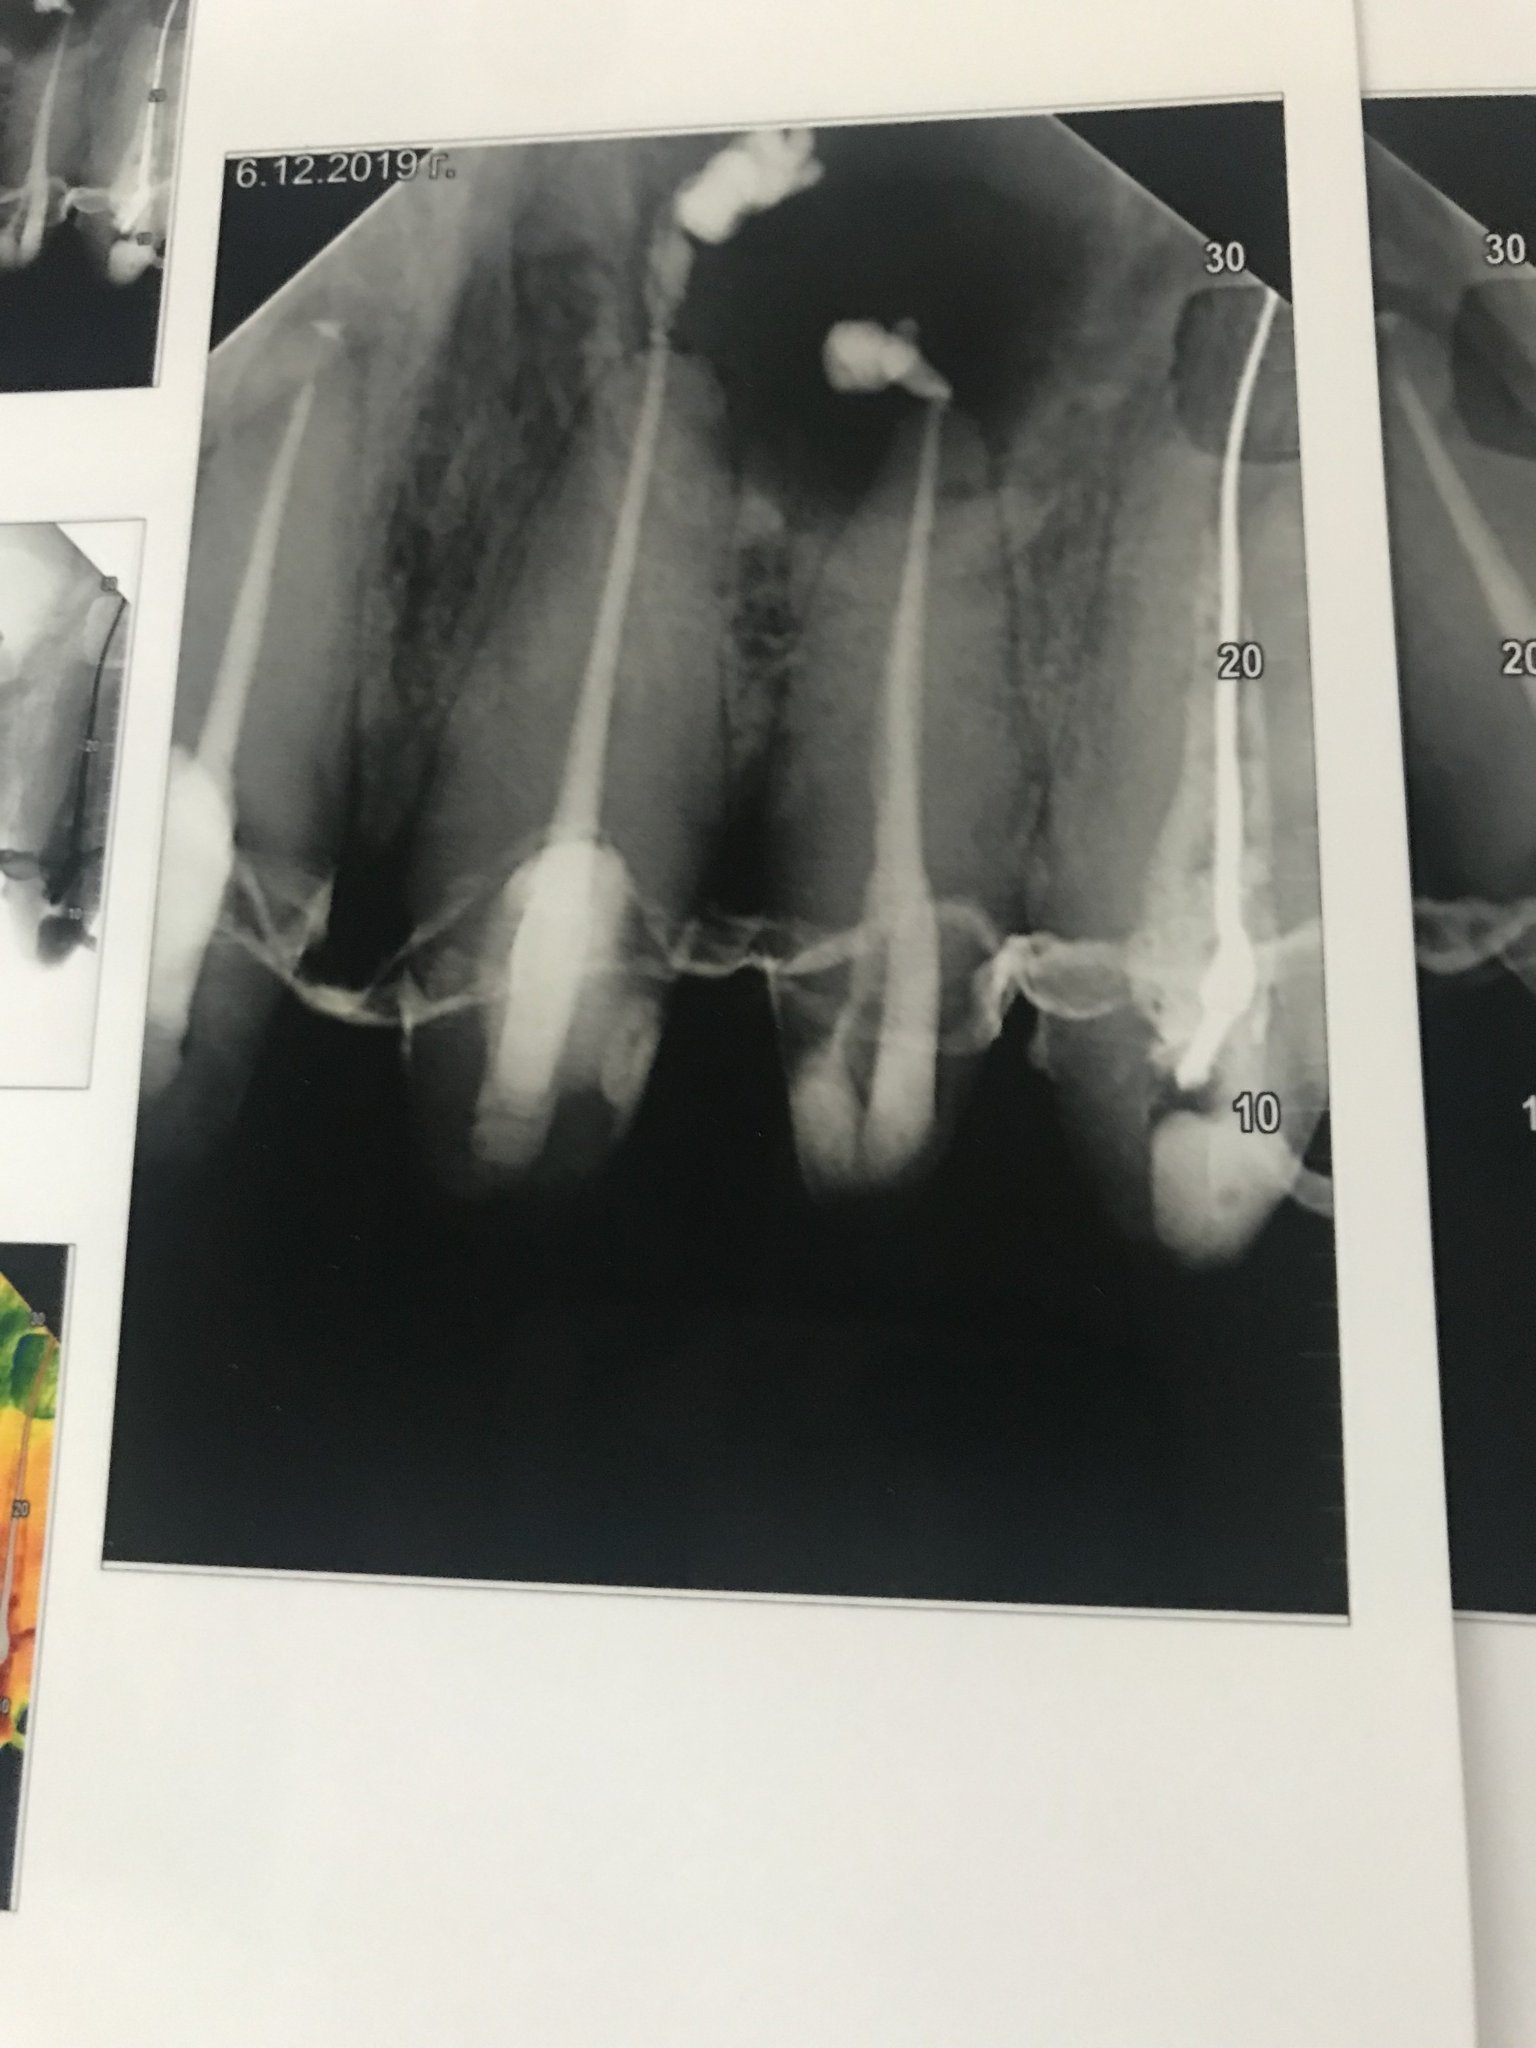

buty, седмият зъб е с лошо кореново лечение, около предните корени изглежда разширено пародонталното пространство, но има и костен дефект (джоб) между 7 и 8 зъб.

Горните срещуположни зъби имат лоши и дълбоки възстановявания (пломби).